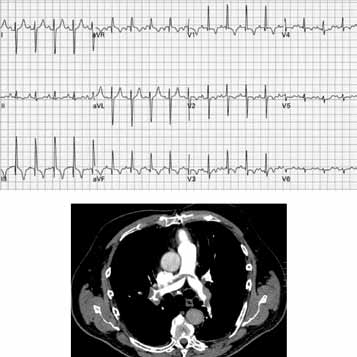

Foram solicitados eletrocardiograma de repouso e tomografia computadorizada de tórax, que se encontram ilustrados a seguir.

A conduta terapêutica inicial mais apropriada ao caso em questão, além de medidas de suporte como expansão volêmica, oxigenioterapia e monitorização, tendo em vista a apresentação clínica e os achados laboratoriais, eletrocardiográfico e tomográfico, será: